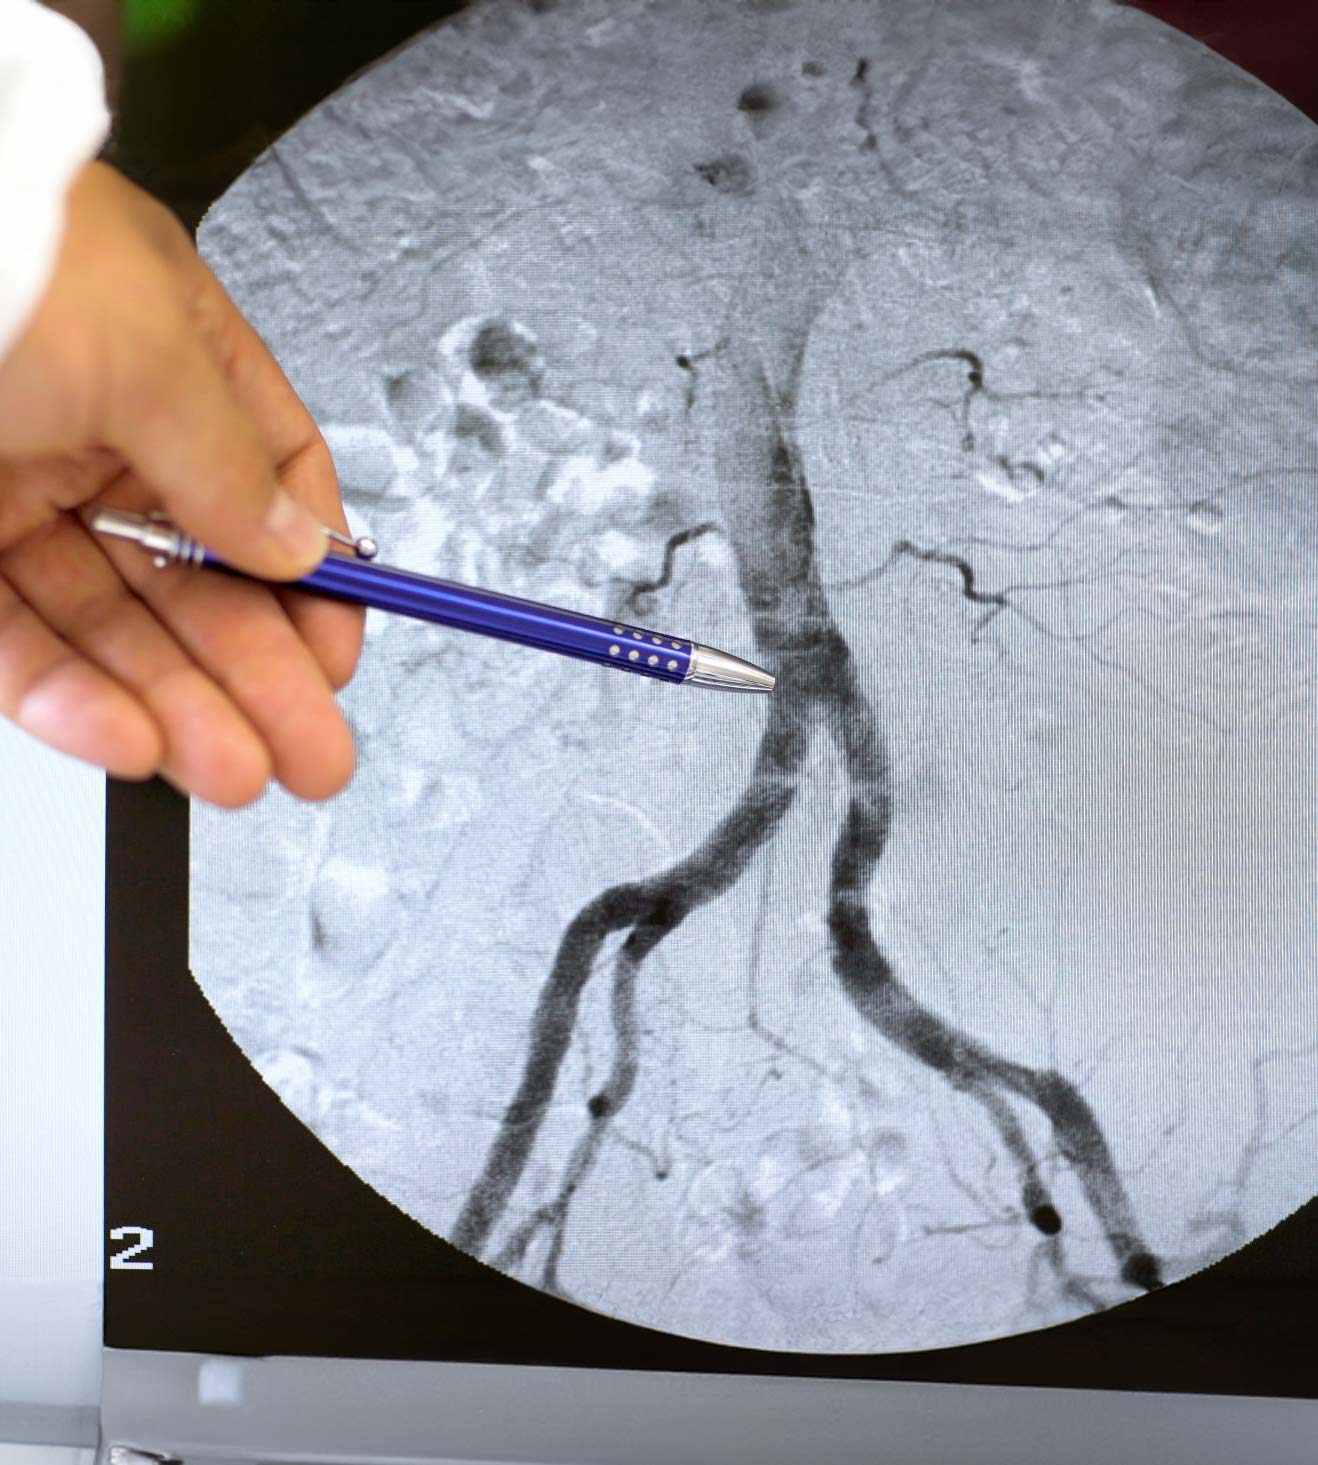

Die Krankengeschichte und der Untersuchungsbefund der Gefäße stellen die Basis jeder Gefäßdiagnostik dar. Bei der Krankengeschichte interessieren z. B. Beinschmerzen beim Gehen, die in Ruhe nicht auftreten. Weil sich diese Schmerzen typischerweise bessern, wenn eine Pause eingelegt wird, bleiben die Patient*innen nach einer bestimmten Wegstrecke immer wieder stehen. Das Phänomen wird daher auch oft als Schaufensterkrankheit bezeichnet. In Kombination mit bildgebenden Ultraschallverfahren können die Flussverhältnisse im Körper direkt beobachtet werden. Diese so genannte Duplex-Sonografie kann an den Halsgefäßen sowie den Beckenbeingefäßen vorgenommen werden. Vielfach machen derartige Ultraschallmethoden eine Gefäßdarstellung mit Kontrastmitteln überflüssig. Der moderne, hochauflösende Ultraschall ist derzeit die beste Methode um Erkrankungen der Venen (z.B. die Thrombose) rasch und sicher abzuklären. Er ist schmerzfrei und benötigt keine Röntgenstrahlung und keine Kontrastmittel. Zusätzlich besitzt er derzeit die höchste bildgebende Auflösung, so dass auch die kleinsten Details sicher erkannt werden können.